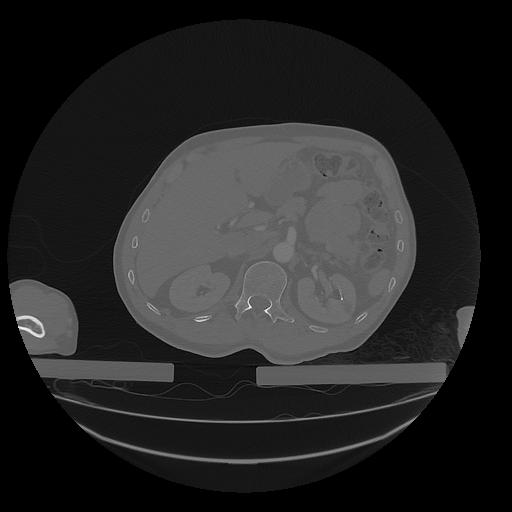

31 PULMON,CE,Vol,1.0,PULMON,,